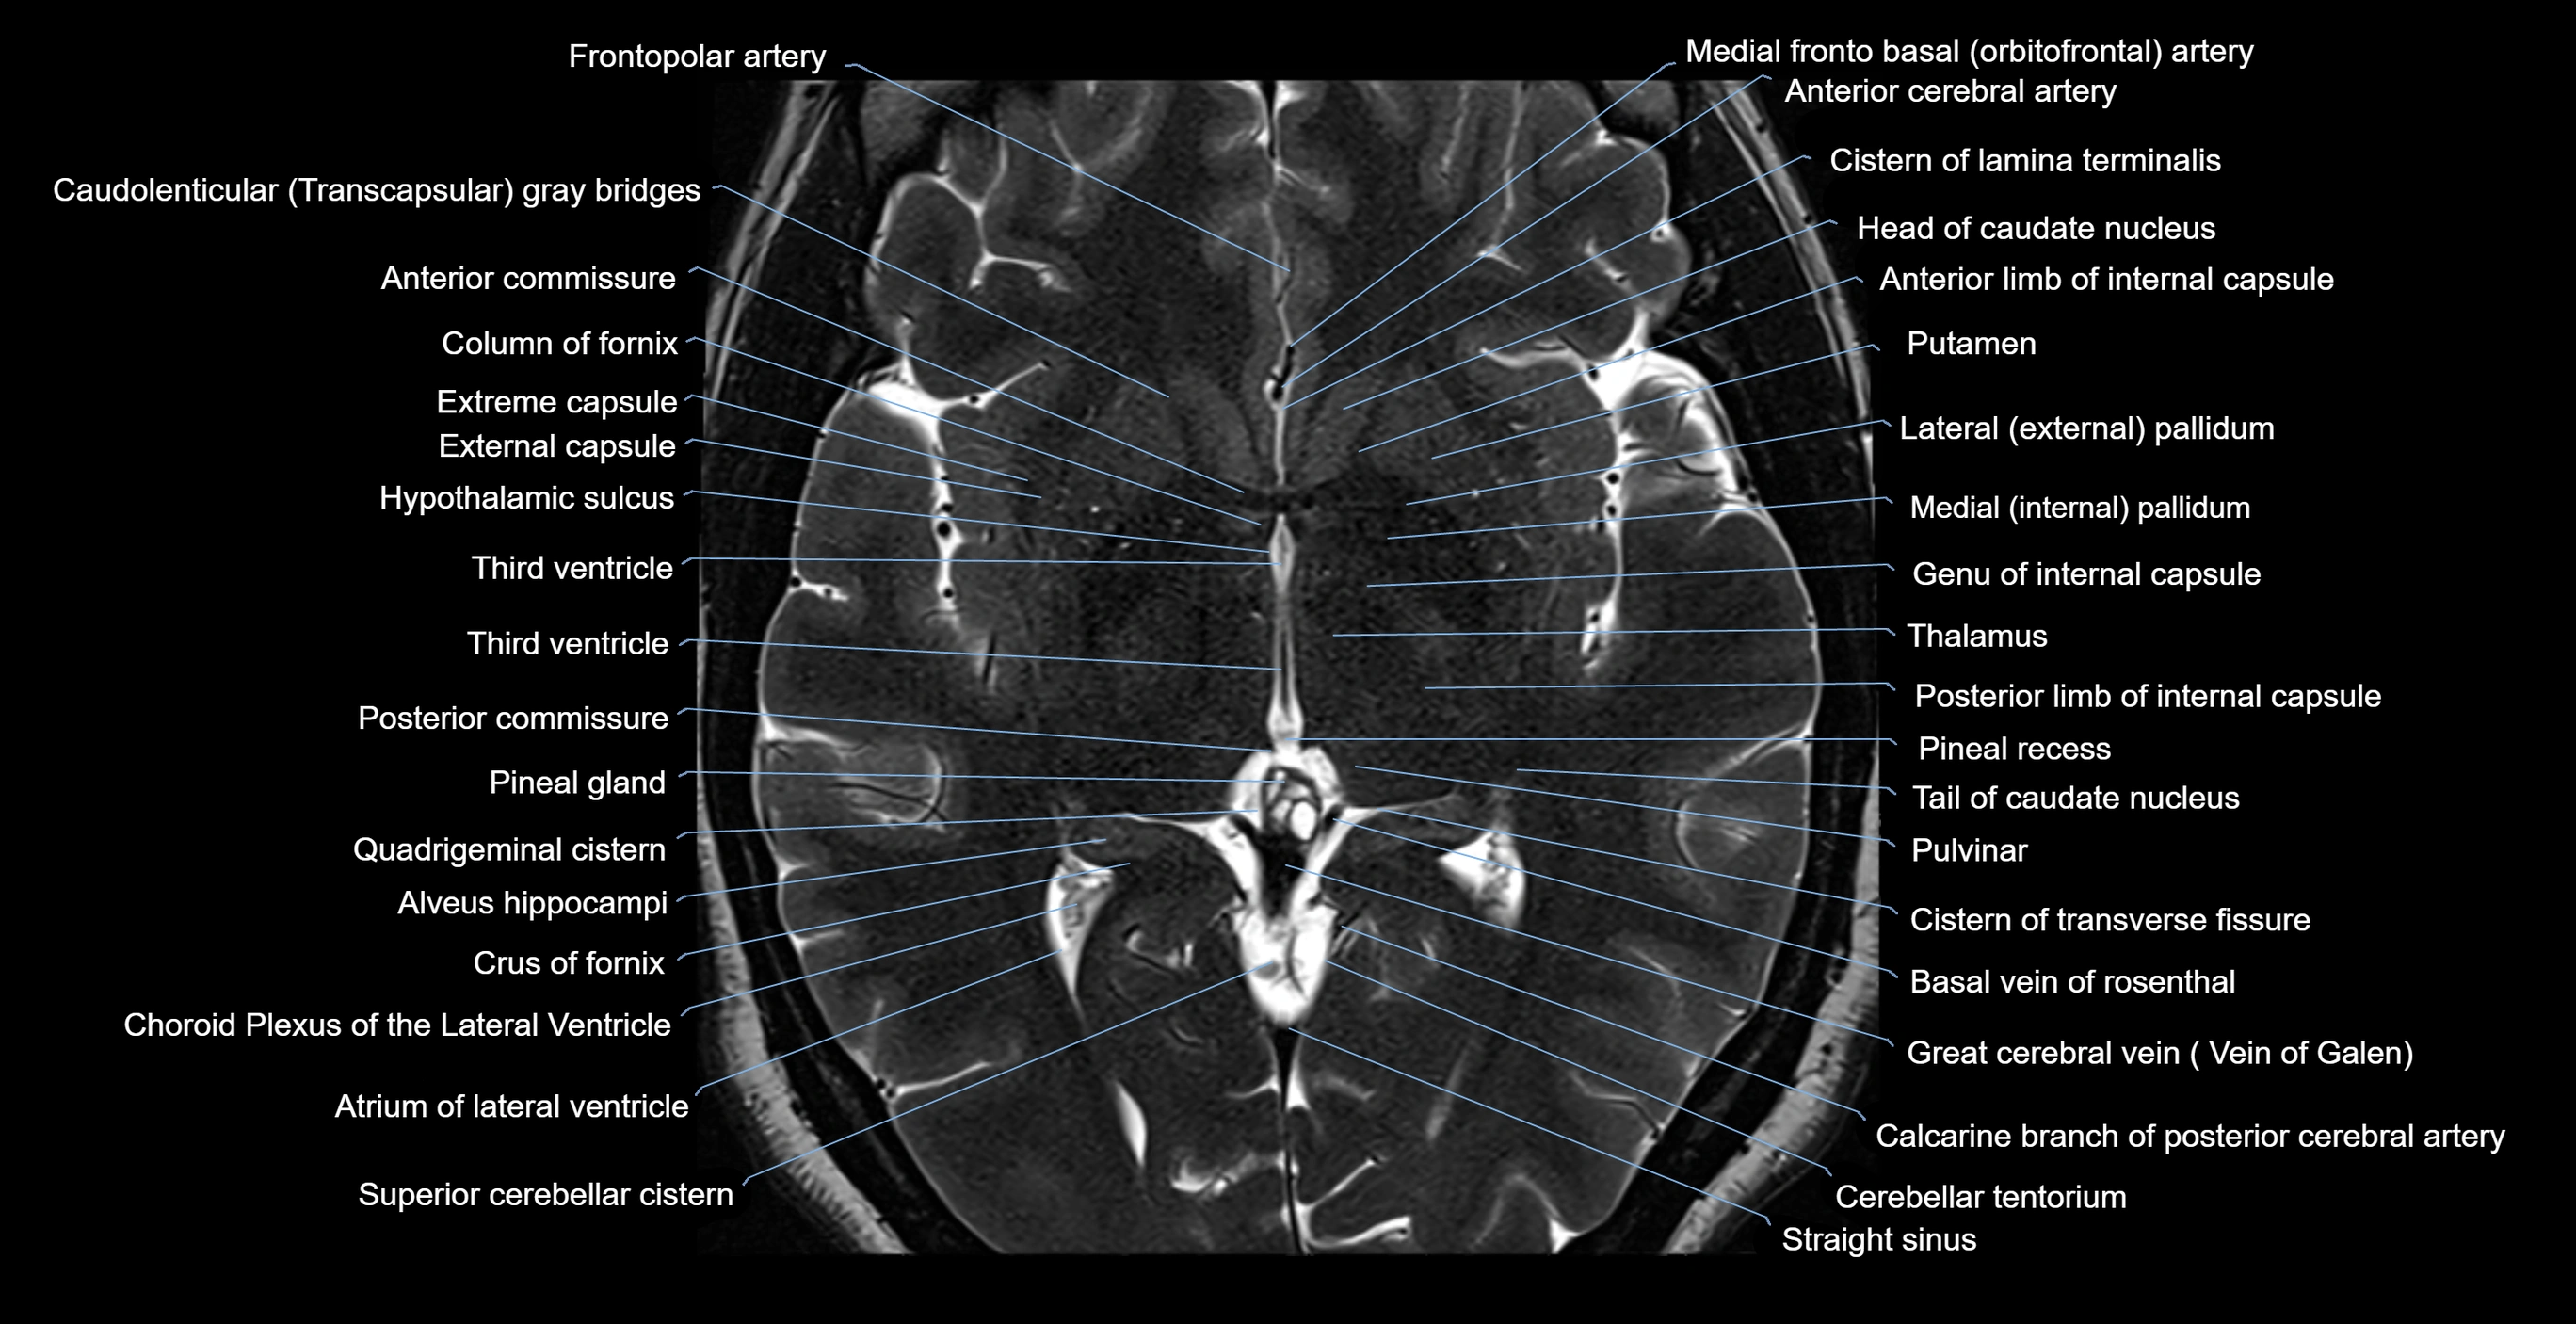

- Anterior commissure

- Atrium of lateral ventricle

- Basal vein of rosenthal

- Body of caudate nucleus

- Choroid plexus of the lateral ventricle

- Column of fornix

- Crus of fornix

- External capsule

- Extreme capsule

- Frontopolar artery

- Globus pallidus external segment

- Globus pallidus internal segment

- Great cerebral vein

- Head of caudate nucleus

- Inferior sagittal sinus

- Internal cerebral vein

- Interthalamic adhesion

- Pineal gland

- Pineal recess

- Posterior commissure

- Pulvinar

- Putamen

- Quadrigeminal cistern

- Straight sinus

- Superior thalamostriate vein

- Tail of caudate nucleus

- Thalamus

- Third ventricle